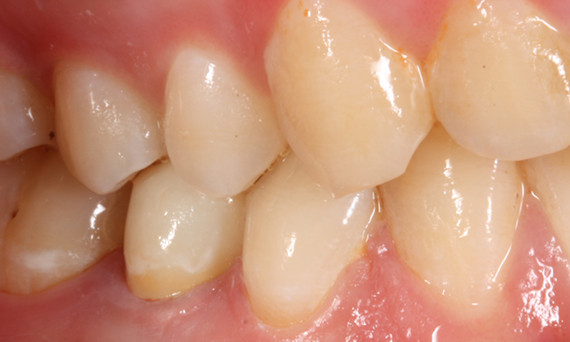

Segundo premolar superior en 90 minutos

Una corona CEREC Zirconia MTL

El paciente estaba muy contento con el tratamiento de conservación del diente en una sola visita. La corona hecha de CEREC Zirconia MTL proporciona alta resistencia y muy buena estética.

Antes: Una lesión mesial cariosa grande en el diente 15. El diente mostró periodontitis apical asintomática y una pérdida significativa de la estructura dental.

Después: Restauración fabricada chairside hecha de CEREC Zirconia MTL diseñada utilizando la función individual biogénica en el software CEREC.